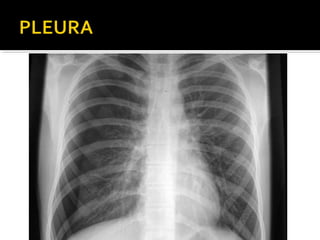

Este documento fornece parâmetros técnicos para realizar uma radiografia de tórax, incluindo posicionamento correto do paciente, dose adequada de radiação e estruturas anatômicas a serem avaliadas, como coração, pulmões, pleura, diafragma e ossos do tórax.